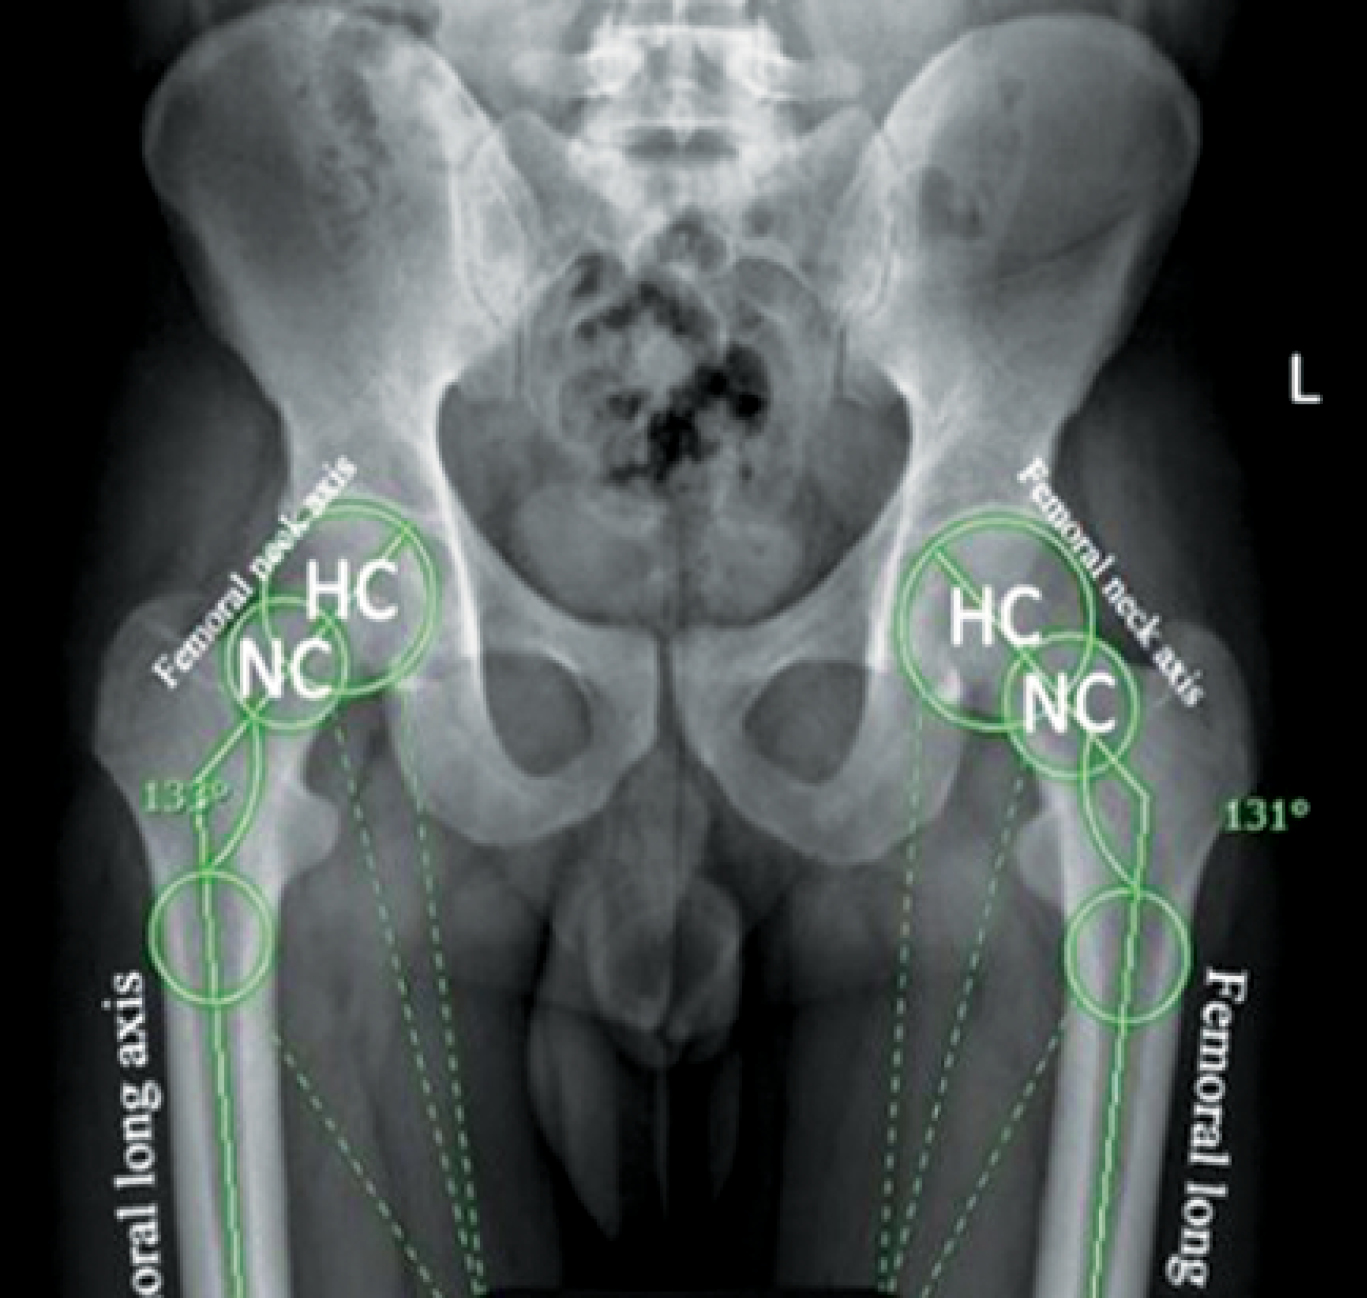

Postoperative evaluation included immediate anteroposterior (AP) and lateral X-rays of the hip. The femoral NSA was determined according to the methodology described by C. K. Boese et al. [10]. This angle was calculated between the axis of the femoral neck and the anatomical axis of the FS. The neck axis was drawn from the femoral head center (HC) to the neck center (NC), the latter defined as the midpoint between points where a circle (centered on the HC) intersected the superior and inferior borders of the femoral neck. The shaft axis was established by connecting central points identified at both proximal and distal segments of the femoral diaphysis [11]. The tip-apex distance (TAD) was calculated as the cumulative length from the screw tip to the apex of the femoral head as seen on both the AP and lateral projections [12]. FS lateralization was assessed by measuring the horizontal distance from the femoral head center to a reference line parallel to the lateral cortex of the femur, comparing the injured side with the contralateral uninjured side [7] (Figures 1, 2).

Figure 1. Neck-shaft angle measurements on an upright pelvis plain X-ray

No significant difference in neck shaft angles was observed postoperatively compared to the contralateral side in either PFN or DHS groups (Table 4, Figures 3, 4).

Mean±SD | 131.30±4.54 | 134.70±3.77 | 0.109 |

Range | 123-139 | 126-140 |